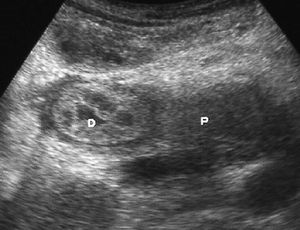

El duodeno es una localización infrecuente de diverticulitis. La imagen radiológica consiste en un engrosamiento de la pared del duodeno asociado a un divertículo, en ocasiones con un enterolito en su interior, con inflamación de la grasa adyacente16 (fig. 9).

Fig. 9--Diverticulitis duodenal. (A) En la ecografía se observa un divertículo (flechas) con engrosamiento de pared duodenal (D) y alteración de la grasa adyacente (*). (B) Tomografía computarizada de otro paciente con inflamación de divertículo duodenal. Se oberva una lesión quística (punta de flecha) de pared gruesa y borrosa, con material en su interior. P: Páncreas.